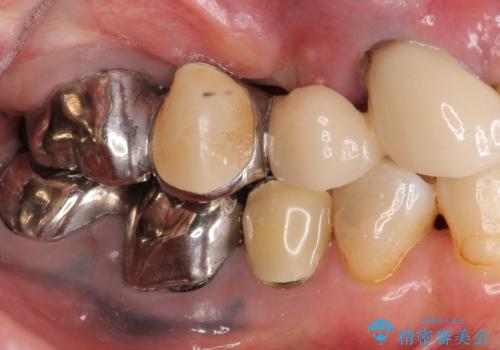

・再発した虫歯

・銀歯の下にできた虫歯

・根尖性歯周炎

・残根状態の歯

など、虫歯を原因とする問題が多発した状態です。

今後延々と治療を繰り返さないために、全ての銀歯を外し虫歯を丁寧に取り切り、根管治療を行い、残せない歯は抜去を行った上でインプラント治療を行っていくことで全体的な治療を計画していくこととなりました。